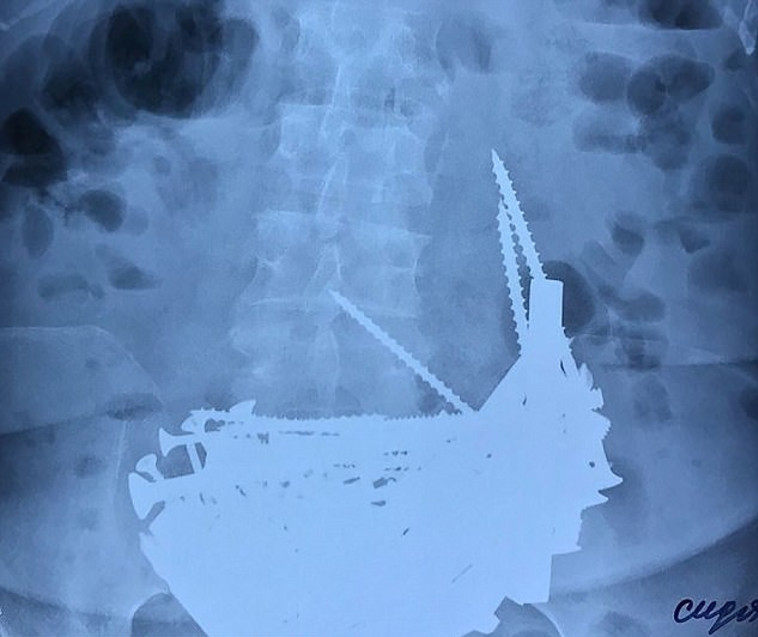

צילום הרנטגן של בטנה של נינה. צילום מסך

צילום הרנטגן של בטנה של נינה. צילום מסך | צילום הרנטגן של בטנה של נינה. צילום מסך